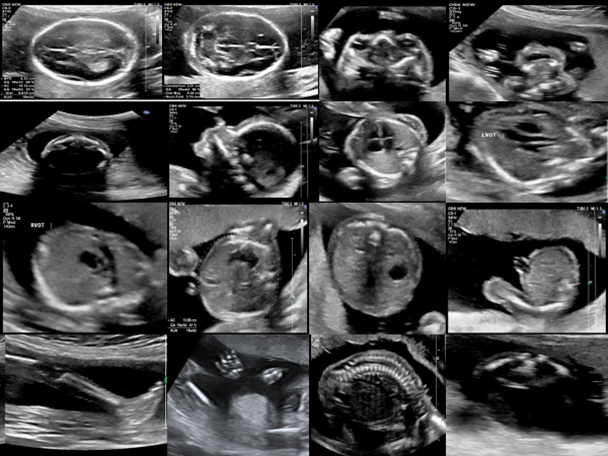

Anomaly ultrasound is a mid-trimester scan performed between 18–22 weeks of gestation to evaluate fetal anatomy and detect structural malformations. It systematically examines fetal brain, heart, kidneys, limbs, and spine. Normal amniotic fluid is essential for fetal development; amniotic fluid index (AFI) normally ranges 8–24 cm, and single deepest pocket ranges 2–8 cm. Abnormalities in volume may indicate oligohydramnios or polyhydramnios.

Anomaly ultrasound is a detailed mid-trimester scan done at 18–22 weeks to evaluate fetal anatomy, placental position, and intrauterine environment. It checks structural integrity of the fetus, placenta, cord, and fluid volume. Normal amniotic fluid index (AFI) ranges 8–24 cm, with a single deepest pocket of 2–8 cm. The exam screens for congenital malformations, multiple gestations, and growth patterns.

1. Fetal heart structure is assessed, including the four-chamber view and outflow tracts, to detect congenital cardiac defects.

2. Placental position is evaluated to identify placenta previa, accreta spectrum risk, or abnormal insertion sites.

4. Amniotic fluid volume is measured to detect oligohydramnios (AFI <5 cm) or polyhydramnios (AFI >24 cm), which affect fetal development.